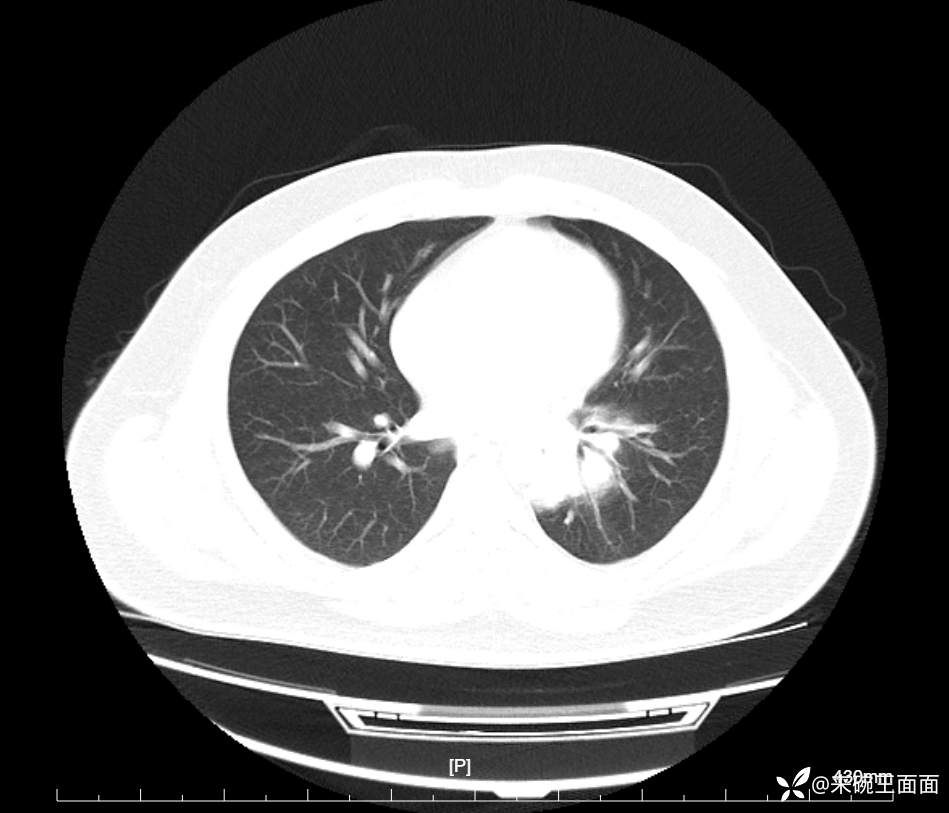

性别:男

年龄:27岁

主诉:胸闷胸痛数月余,休息后可自行缓解,无咯血症状。

个人史:数年吸烟史,具体不详。